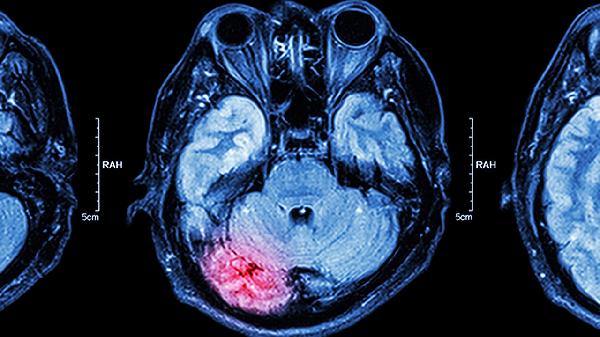

由病毒或细菌感染引起,除颈部强直疼痛外,多伴有高热、喷射状呕吐、意识模糊等全身症状。需紧急就医进行腰椎穿刺确诊,使用注射用头孢曲松钠抗感染,甘露醇注射液降低颅内压。该病具有传染性,确诊后需隔离治疗。